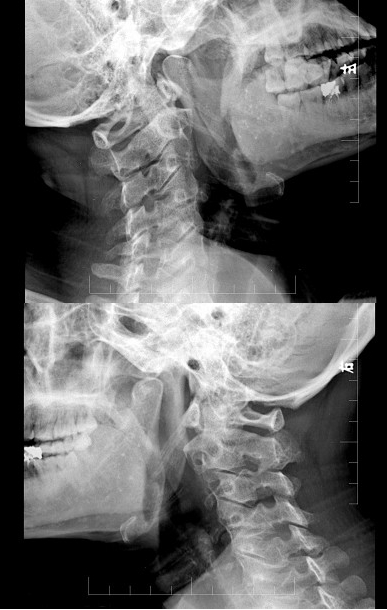

男,35岁,反复颈部不适20余年,结合图像,最可能的诊断是()

A.颈椎椎体融合

B.颈椎结核

C.颈椎退行性变

D.颈椎压缩性骨折

E.颈椎骨转移瘤

194、单项选择题 下列有关摄影体位命名原则的描述,错误的是()